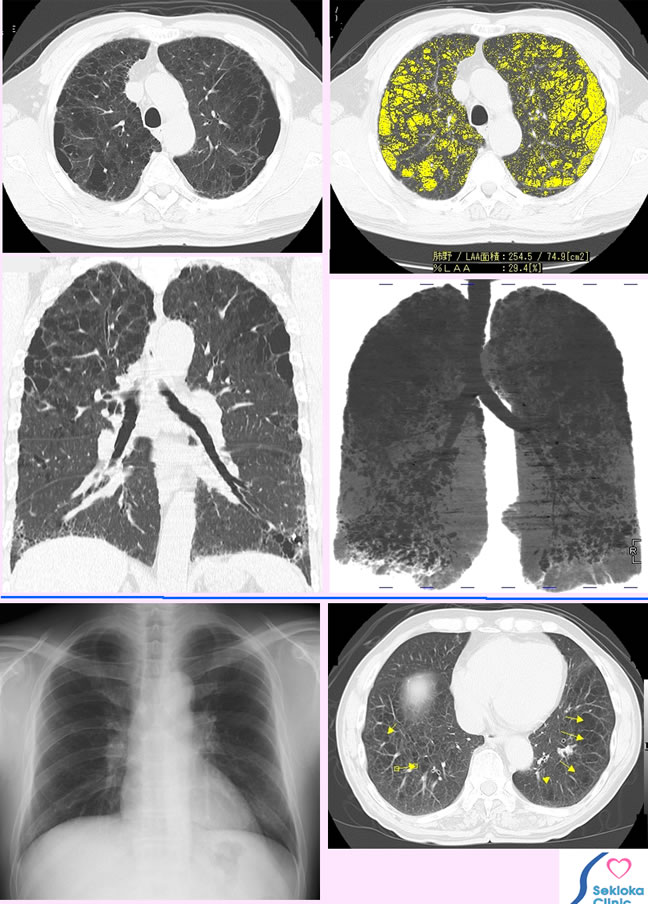

| 診断 | 薄いスライスのCT撮影。 MDCTは高速に薄いスライスを多数枚撮影でき、全肺野を検査するのに適しています。X線撮影は肺気腫の診断に無力。最下段に示す胸部X線撮影では正常に見えますが CTでは明瞭に肺気腫が示されれています。当然、肺がん健診の胸部X線撮影も肺気腫の診断はできません。CTの画像で黒い泡のように見える部分が肺の正常構造が失われた肺気腫の部分です。上段右側の画像で黄色の部分は コンピュ-タが検索した肺気腫の部分で定量的にその面積 全肺に対する%を表示しています。経時的に病気の進行状況を比較、評価するのに有用です。中段右の画像は肺全体での肺気腫の広がりを示すために画像処理したもので 黒い泡(巣)の様な部分が肺気腫です。 |